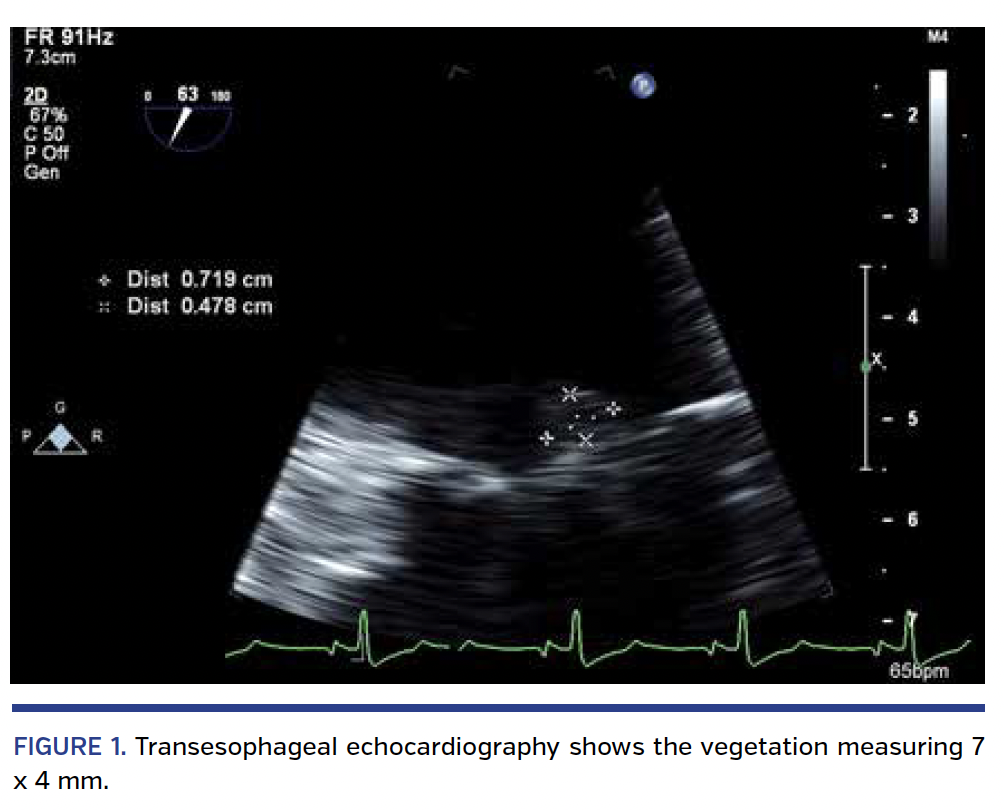

A 75-year-old man with a history of coronary bypass surgery presented with 3 weeks of fever. A transesophageal echocardiogram (TEE) revealed a 7 mm vegetation on the mitral valve with mild-moderate functional mitral regurgitation (MR) (Figure 1; Videos 1 and 2). After 4 weeks of antibiotics, he presented with New York Heart Association class III dyspnea and repeat TEE demonstrated severe MR (Figure 2; Videos 3 and 4) with the anterior leaflet thickened and retracted with resultant malcoaptation (Videos 5 and 6). Magnetic resonance imaging of the brain showed 2 acute lacunar infarcts. On hospital day 3, he developed profound dyspnea with hypotension and acute renal failure. The patient remained dyspneic and anuric despite maximal medical support. Dialysis was initiated. Surgery was considered prohibitive due to multiple comorbidities. After consultation with Infectious Diseases, it was determined the infection risk was low and transcatheter mitral valve repair (TMVR) was offered.